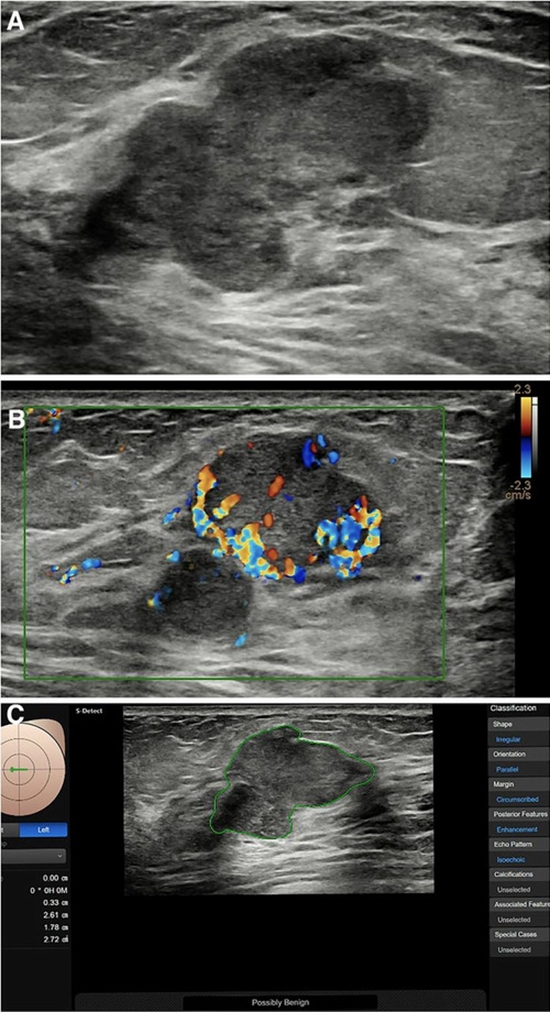

بررسی میزان ارزش اخباری مثبت برای سرطان پستان درضایعات بایردز 4a در بیماران مراجعه کننده به انیستیتو کانسر

بررسی میزان ارزش اخباری مثبت برای سرطان پستان درضایعات بایردز 4a